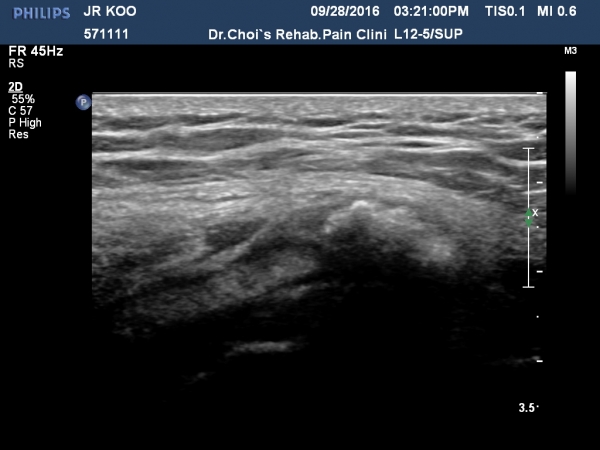

´ëÀüÀÚ Á¾´Ü¸é°Ë»ç¿¡¼­ ¼ÒµÐ±Ù¿¡ ¼®È¸È­À½¿µÀÌ °üÂûµÊ(»çÁø 3, 4).